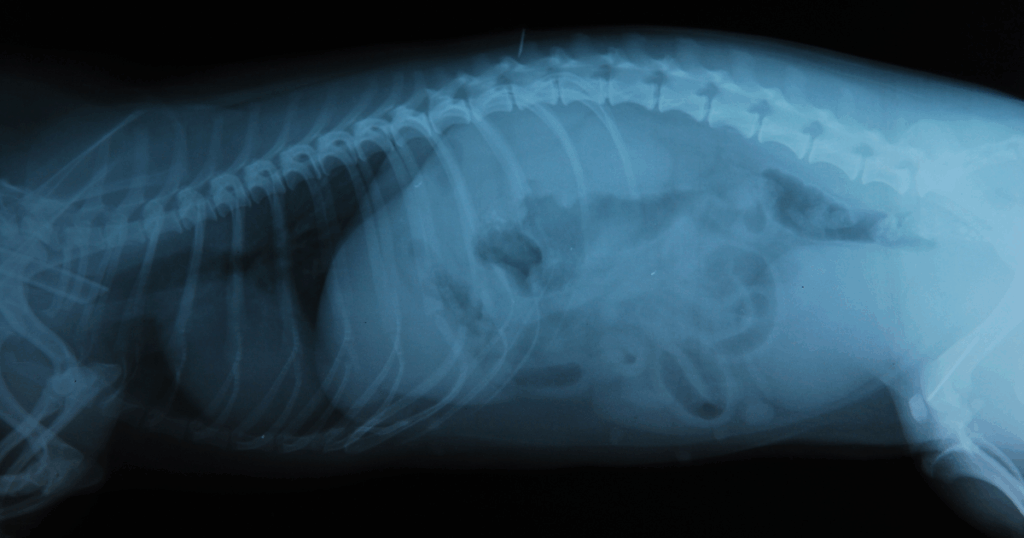

Presso la Clinica Veterinaria Zarcone 24H è presente un’unità specializzata in Radiologia Digitale, che consente di eseguire radiografie ad alta definizione in tempi molto rapidi, grazie a software avanzati che elaborano le immagini immediatamente sul computer.

Le radiografie digitali rappresentano sono fondamentali nella diagnostica veterinaria, in quanto offrono un primo approccio rapido ed efficace per individuare la causa del disturbo del paziente.

Le radiografie digitali consentono di ottenere immagini chiare e dettagliate in pochi secondi, garantendo una qualità superiore rispetto ai sistemi tradizionali. L’acquisizione immediata dell’immagine permette una refertazione rapida, riducendo significativamente i tempi di attesa e migliorando l’efficacia del processo diagnostico.

Sono particolarmente utili per la diagnosi di:

- problemi scheletrici e articolari

- patologie toraciche (cuore, polmoni)

- alterazioni dell’apparato gastroenterico

- traumi e fratture